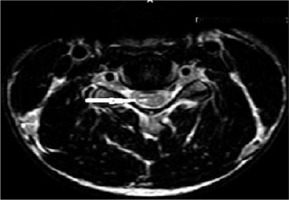

Figure 3

T2W axial image at the level of the pedicle in a 16-year-old male with Hirayama disease, showing loss of attachment of the dura (arrow), which is more than one-third, as shown by lines dividing the lamina into 3 equal parts

Axial T2TSE images were evaluated for loss of attachment (LOA) between the posterior dural sac and adjacent lamina on each side from level C4 to C6. The degree of separation was evaluated by a method given by Chen et al. [13]. Medial extent of the lamina was defined by the point of junction with the opposite lamina and laterally by a tangential line along the medial aspect of the pedicle. This was divided into 3 equal parts (Figure 2). LOA was considered present when the dural separation was greater than one-third of an adjacent lamina (Figure 3). This finding at a single level on one side was considered sufficient to score the presence of LOA [2].

LOA of posterior dura with anterior displacement was seen in all the patients (100%) on flexion MRI (Figure 7). LOA involved the whole of the posterior dura (bilateral) in 13 patients (76.4%) and only one side in 4 patients (23.5%). Maximum LOA was seen at the C6 level in 10 patients (58.8%), followed by C5-6 intervertebral disc level in 5 patients (29.4%), and C5 and C6-7 level in one patient each (5.8%). This LOA of the posterior dura was seen in 11 patients (64.7%) on neutral position MRI, as well (Figures 8 and 9). On evaluating axial T2W and T2 FFE images for LOA of posterior dura, mutual consensus was reached by 2 radiologists that it was better visualised on T2 FFE images (Figure 9). The mean thickness of this LOA on flexion was 3.7 ± 0.66 mm (mean ± 2SD).

Asymmetrical lower cervical cord atrophy is the most important imaging feature on neutral MRI that can suggest the diagnosis of HD. LOA can also be seen on neutral MRI. On evaluating neutral T2W axial images in our study, LOA was seen to be present in 64.7% of the patients. As per Chen et al. [13], LOA was the most effective finding in the diagnosis of HD in neutral position MRI, with sensitivity and specificity greater than 93.5%; however, Lehman et al. reported lower sensitivity (70%) of this finding [18].